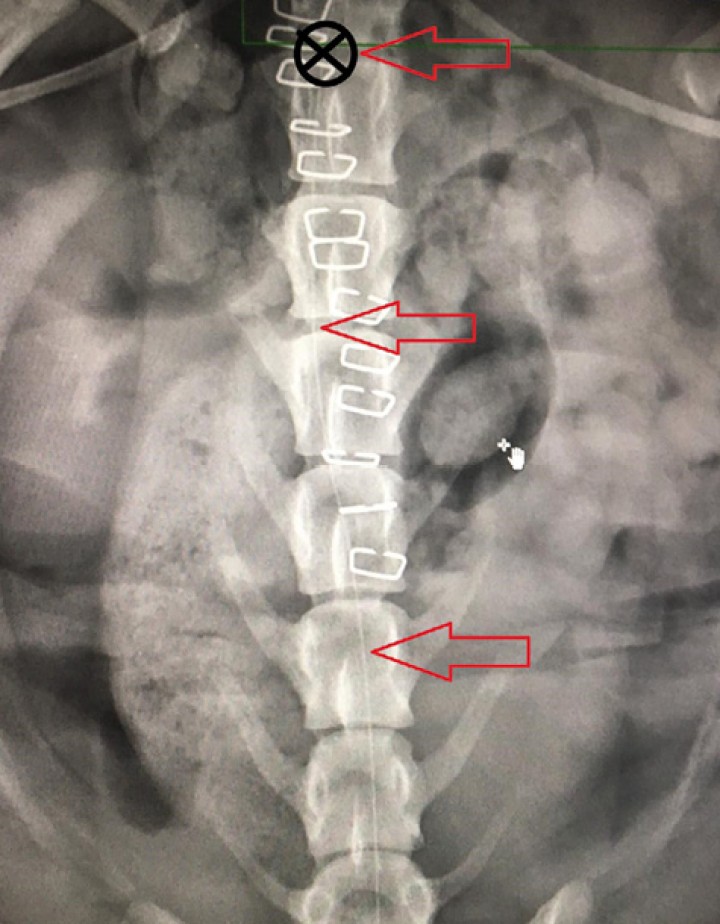

<p>Imagen radiológica en la que se identifica el catéter epidural (flechas rojas) y su posición final (cruz negra) en la vértebra L2.</p>

Figura 3

Imagen radiológica en la que se identifica el catéter epidural (flechas rojas) y su posición final (cruz negra) en la vértebra L2.

Tras la cirugía, el animal fue transportado todavía bajo anestesia general a la sala de radiología para la colocación de un catéter epidural (Perifix, BBraun, Melsungen, Alemania). De manera aséptica se introdujo una aguja Tuohy de 18G (Perican, Bbraun, Melsungen, Alemania) en el espacio sacroccocígeo, reduciendo, mediante este abordaje, la posibilidad de colocación inadvertida en el espacio subaracnoideo. El correcto posicionamiento de la aguja se verificó mediante ecografía (M-turbo, Sonosite, WA, EEUU). Se observó el desplazamiento craneal de una corriente de suero estéril inyectada a través de la aguja en un corte transversal del espacio intervertebral entre L6 y L7. Una vez verificada la posición de la aguja, se introdujo el catéter epidural, observando su desplazamiento en el espacio epidural mediante ecografía en corte transversal (Fig. 2). La punta del catéter epidural se llevó hasta el cuerpo vertebral de L2. Se confirmó la correcta colocación a este nivel radiográficamente gracias a la administración de una pequeña cantidad de contraste radiológico yodado (Iomeron, Bracco Imaging, Milán, Italia) a través del catéter epidural (Fig. 3). Finalmente, se tunelizó el catéter epidural por el tejido subcutáneo y se fijó en la zona lumbosacra (Fig. 4).